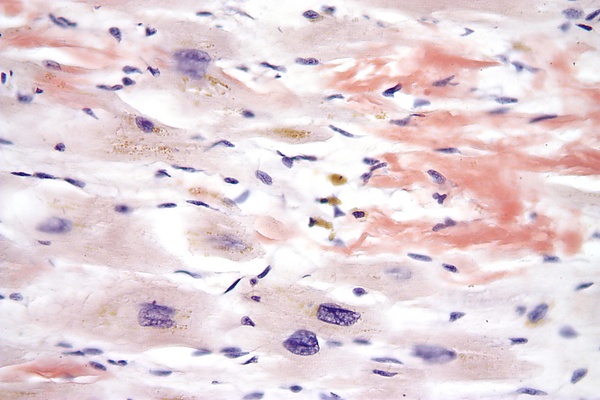

Патофизиология

Инфильтрация миокарда или его утолщение может встречаться в одном (чаще в левом) или обоих желудочках. В связи с этим развивается нарушение функций митрального или трехстворчатого клапана, что приводит к регургитации. Возможно развитие дисфункции синоатриального (СА) и атриовентрикулярного узлов, что может приводить к различным степеням СА-блокады и АВ-блокады.

При данной группе заболеваний происходит выраженное ограничение заполнения желудочков во время диастолы и постепенное уменьшение размеров полости желудочков, вплоть до их облитерации[3].